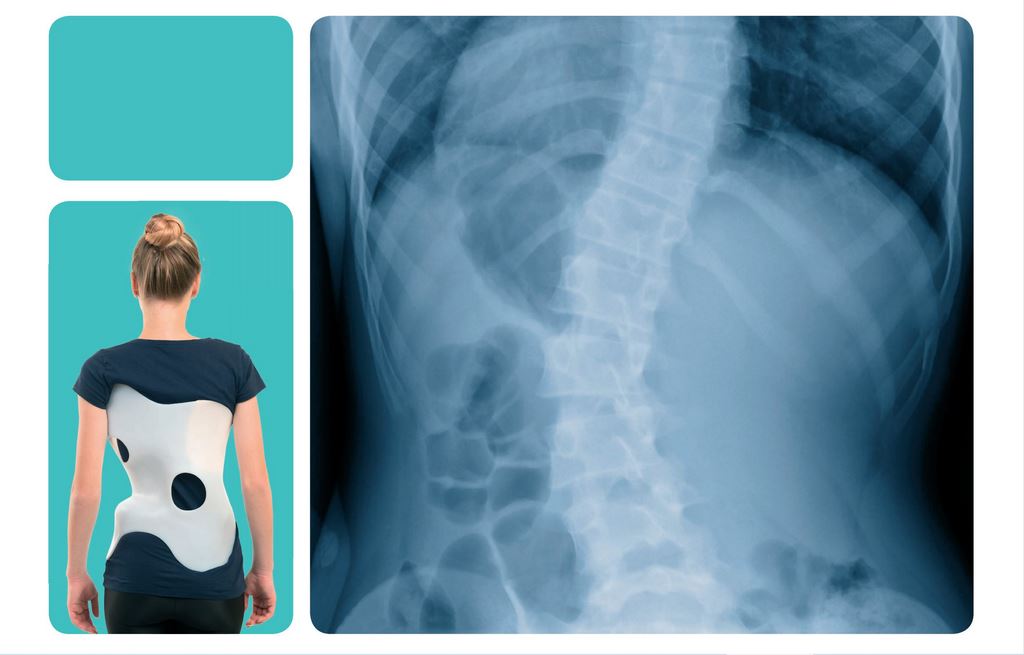

Jeżeli kąt skrzywienia przekroczy 25 º lub gdy następuje duża progresja przy niższych wartościach kątowych zalecaną metodą leczenia jest stosowanie ortezy tułowia typu Rigo Cheneau. Gorset jest indywidualnym zaopatrzeniem ortopedycznym. Jego działanie polega na zastosowaniu trójwymiarowej korekcji deformacji kręgosłupa opierającej się o trójpunktowy rozkład sił oddziałujących na tułów. Korekcję uzyskuję się poprzez zastosowanie pelot uciskowych i obszarów odciążających w płaszczyźnie czołowej, poprzecznej oraz strzałkowej. Gorset korekcyjny umożliwia dwa rodzaje korekcji – czynną i bierną. Korekcja czynna przeciwdziała progresji skrzywienia oraz wzmacnia prawidłową strukturę mięśniową. Korekcja bierna umożliwia tzw shift czyli przesunięcie boczne tkanek za pomocą pelot oraz zmniejsza patologiczne ustawienie kręgów.

W Pomorskim Centrum Protetyki i Ortotyki Narządu Ruchu Ortomax gorsety korekcyjne wykonujemy metodą CAD/CAM. Na pierwszej wizycie pobierany jest skan pacjenta oraz badanie wykonywane przez fizjoterapeutę. Na kolejnej następuje już przymiarka gorsetu połączona z odbiorem. Dzięki zastosowaniu najnowszych technologii nasze gorsety są lepiej dopasowane niż te wykonywane metodą tradycyjną (gipsową). Lokalizacja pelot jest bardziej precyzyjna poprzez zestawienie skanu pacjenta z jego zdjęciem RTG a narzędzia wykorzystywane przy projektowaniu gorsetów pozwalają na uzyskanie większej korekcji skrzywienia przy jednoczesnym zachowaniu wysokiego komfortu. Dużą wagę przykładamy również do jak najniższej wagi ortezy dlatego termoplasty wykorzystywane do produkcji gorsetów są wysokiej jakości. Pozwala to na odpowiednie ich rozciągnięcie podczas termoformowania – uzyskujemy zatem produkt lekki a zarazem odpowiednio sztywny do transferu sił korekcyjnych.